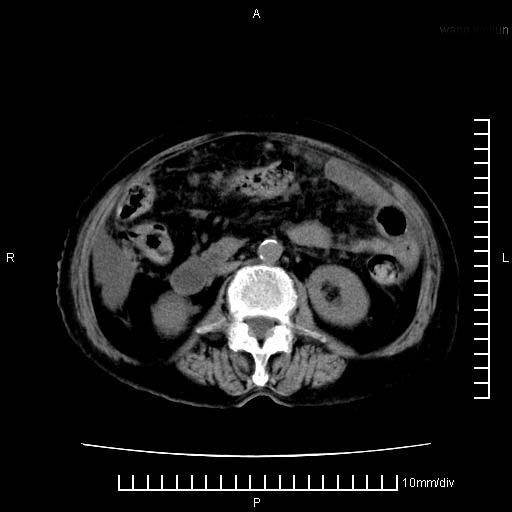

标题: CT28280:腹部增强:女性,80岁

上腹疼痛月余,外院核磁诊断胰腺癌。现临床示右下腹可明显触及包块,可片子上怎么没有看到?

胰腺体部癌累及周围器官,腹膜、粘连

胰腺体部癌累及周围器官,腹膜、粘连,临床摸到的可能是粘的组织

胰腺结构模糊,胰尾部见囊性包块,周围脂肪密度增高,左肾前筋膜增厚,胸水、腹水。不符合胰腺ca伴腹膜腔转移。考虑胰腺炎伴假性囊肿形成、胸腹腔积液。

1、考虑胰腺癌伴腹膜腔转移,胸腹水。

1)考虑胰腺癌并胰腺假性囊肿形成。2)肝内低密度灶,不排除转移。3)右肾盂积水。4)腹水。5)右侧胸腔积液并右肺下叶部分膨胀不全。

右肾盂囊肿。